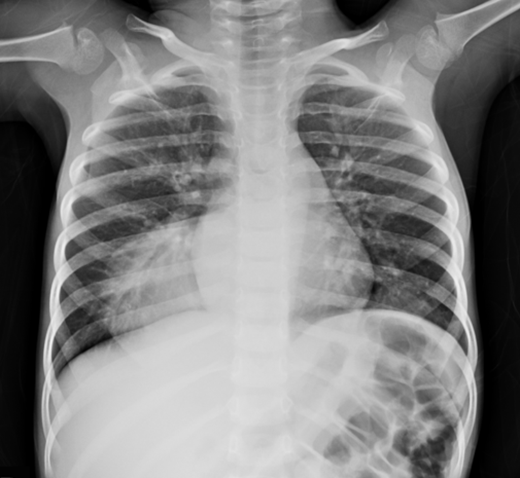

From Chest X-Ray to CT: Diagnosing Right Aortic Arch with Kommerell´s Diverticulum

Humberto Morais, Miguel Vicente, Tshimbalanga Merite, Mauer Alexandre da Ascensão Gonçalves

bjcr74